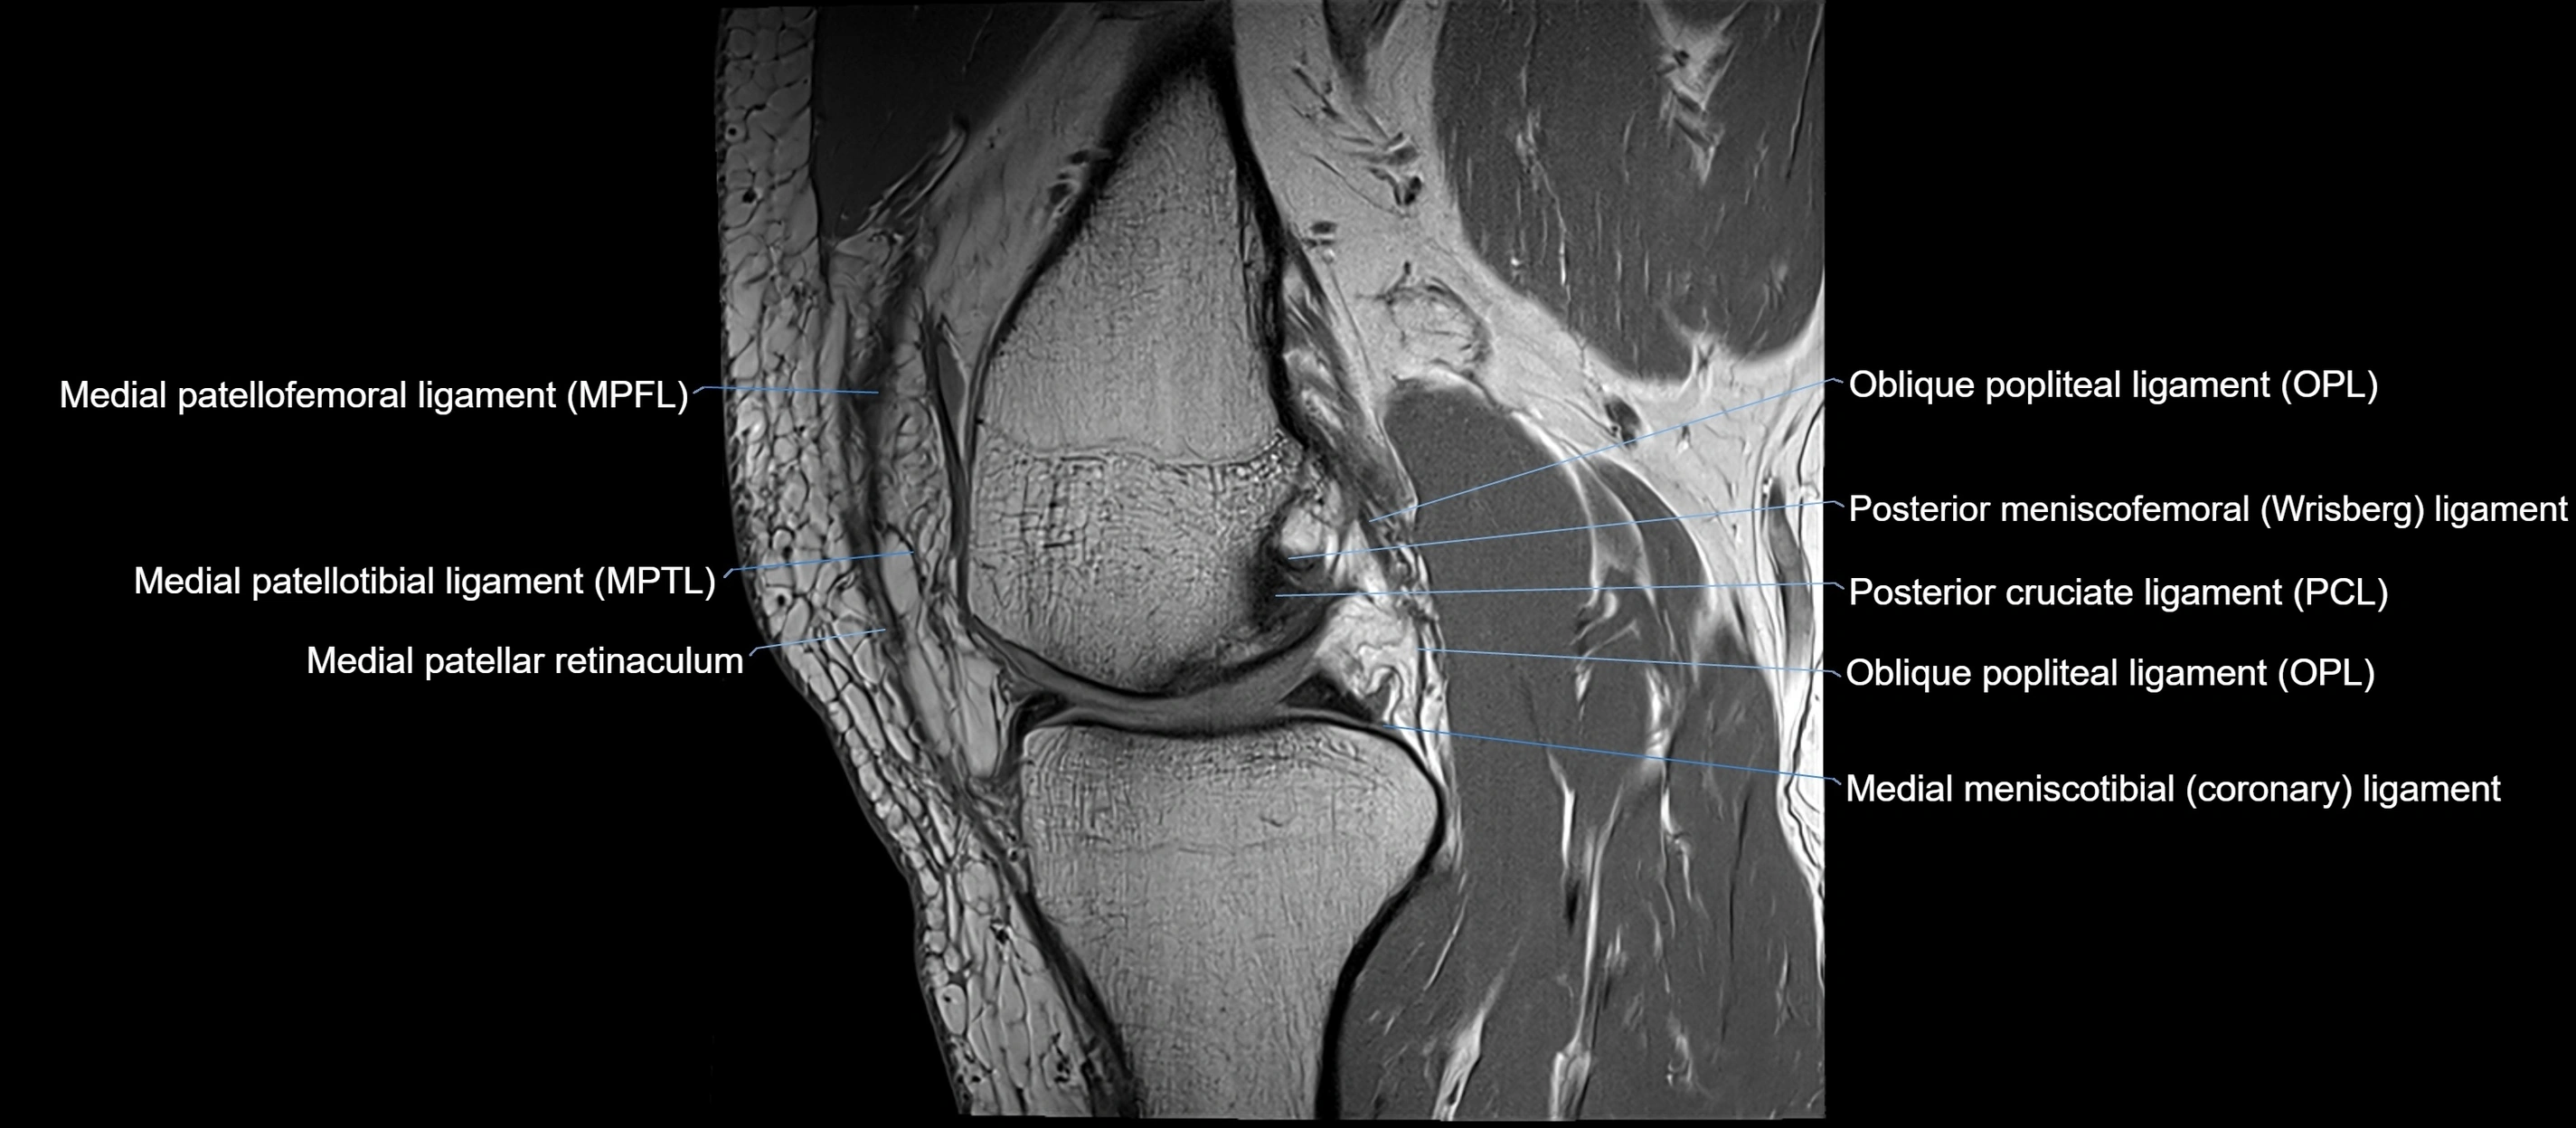

MRI Appearance

T1-weighted images:

• Normal ACL appears as a low-signal band-like structure crossing the intercondylar notch

• Surrounded by intermediate signal synovial fluid and fat planes

T2-weighted images:

• Normal ACL remains low signal

• Partial or complete tears appear as discontinuity, increased signal, or fiber laxity

MRI images

image